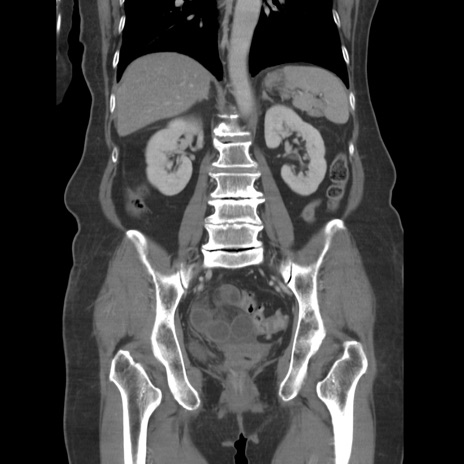

症例19(冠状断像)

【症例】80歳代女性

【主訴】下腹部痛

【現病歴】約8時間前より下腹部痛の出現あり、救急外来受診。

【既往歴】両側付属器切除

【身体所見】意識清明、下腹部正中に手術痕あり、その部位に一致して圧痛と反跳痛あり。腸蠕動音は亢進。

【データ】WBC 9300、CRP 0.15